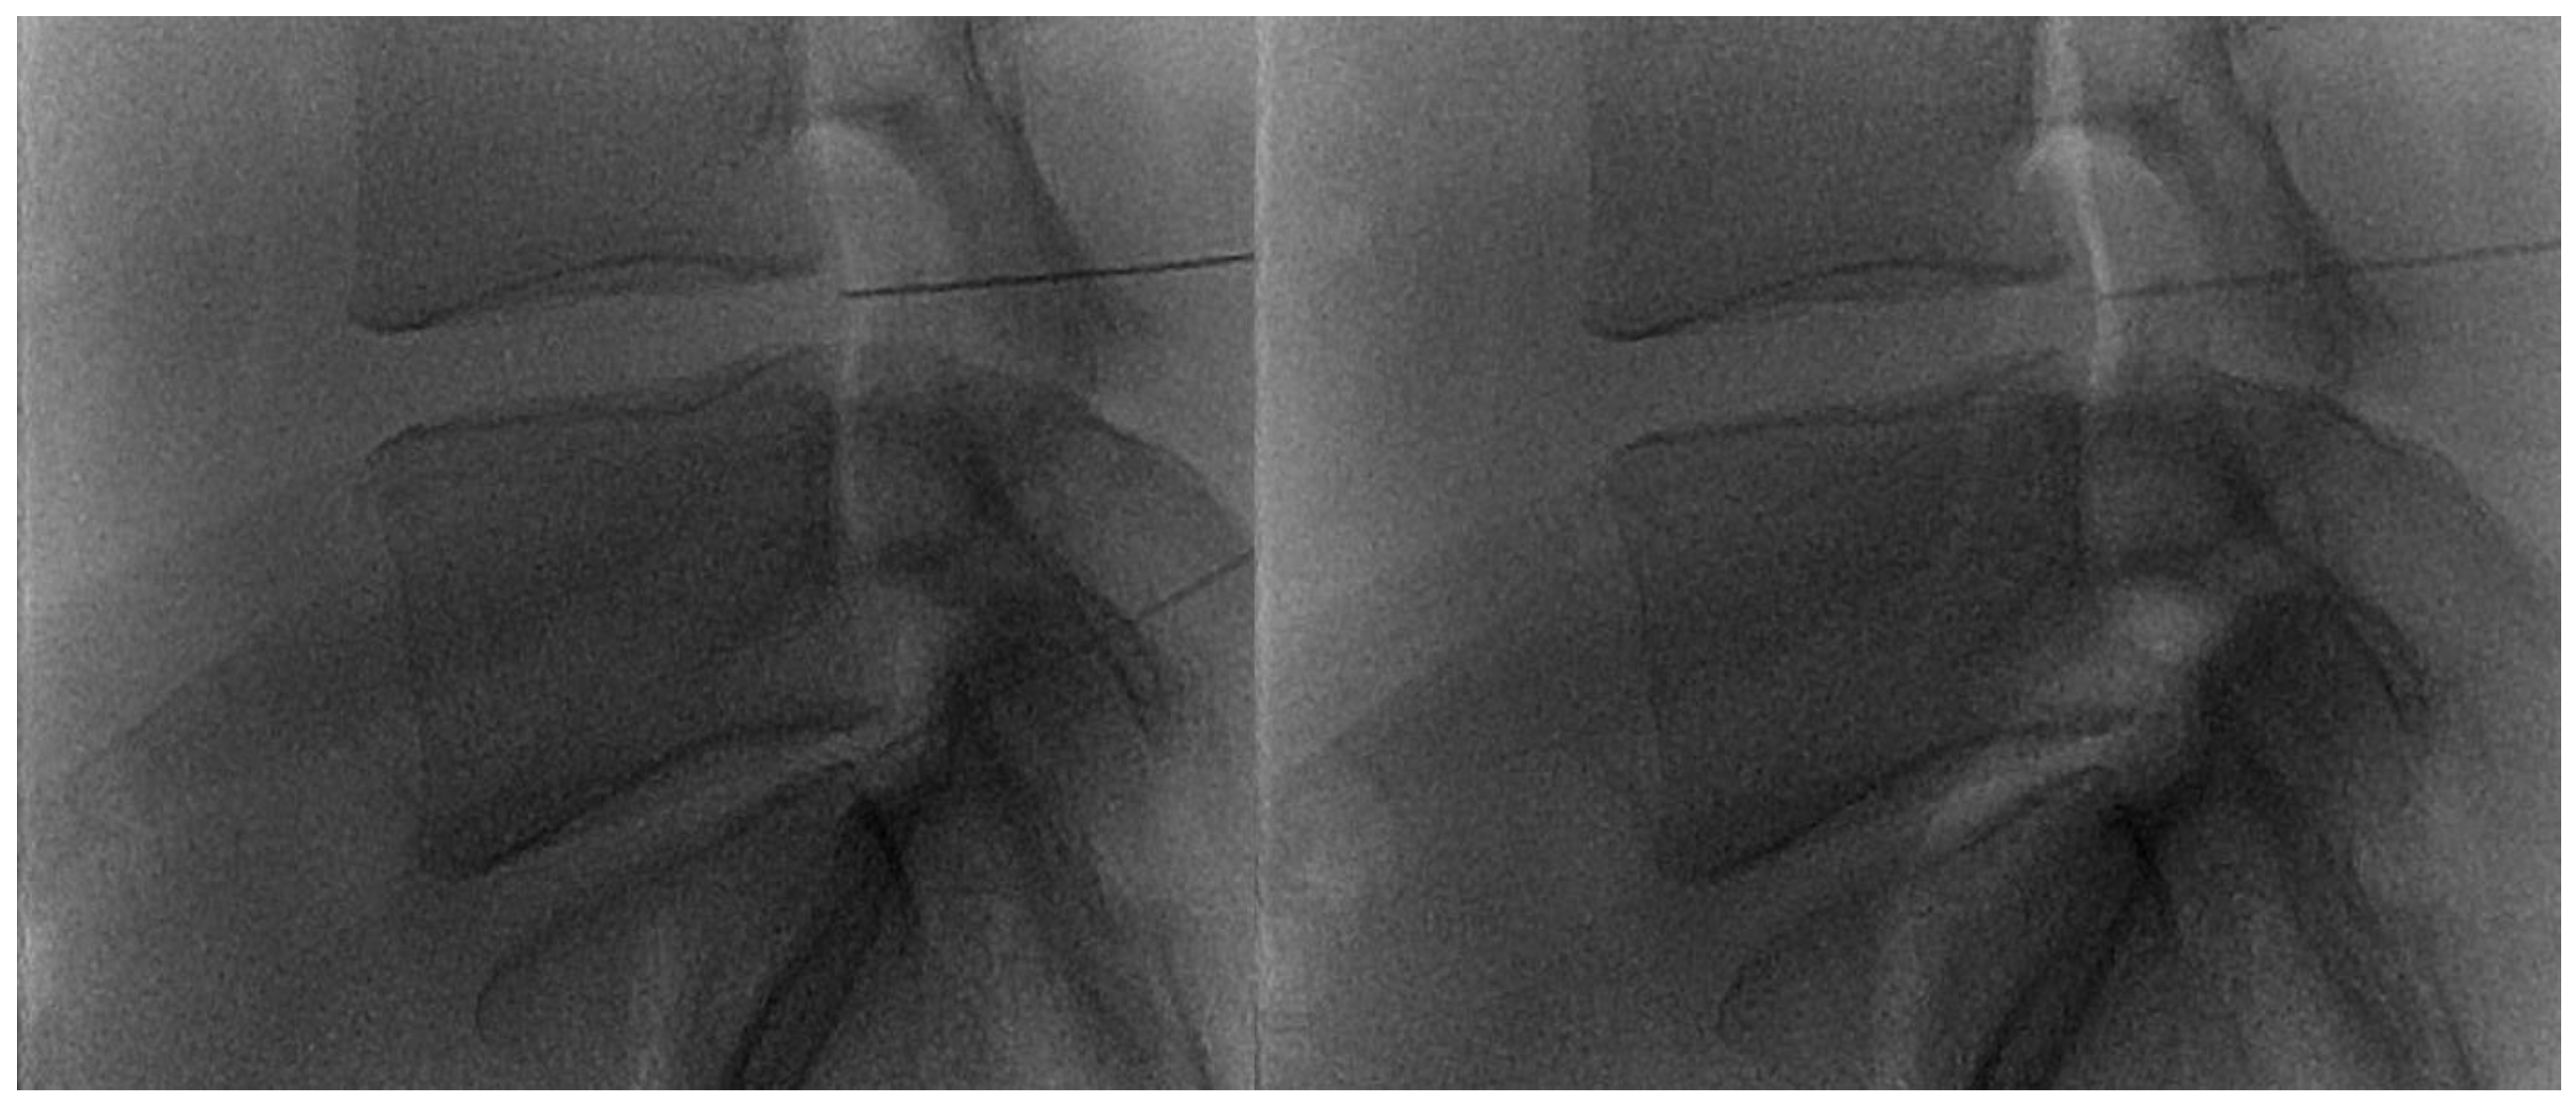

- Napoli, A.; Alfieri, G.; De Maio, A.; Panella, E.; Scipione, R.; Facchini, G.; Albisinni, U.; Spinnato, P.; Nardis, P.G.; Tramutoli, R.; et al. CT-Guided Pulsed Radiofrequency Combined with Steroid Injection for Sciatica from Herniated Disk: A Randomized Trial. Radiology 2023, 307, e221478. [Google Scholar] [CrossRef] [PubMed]